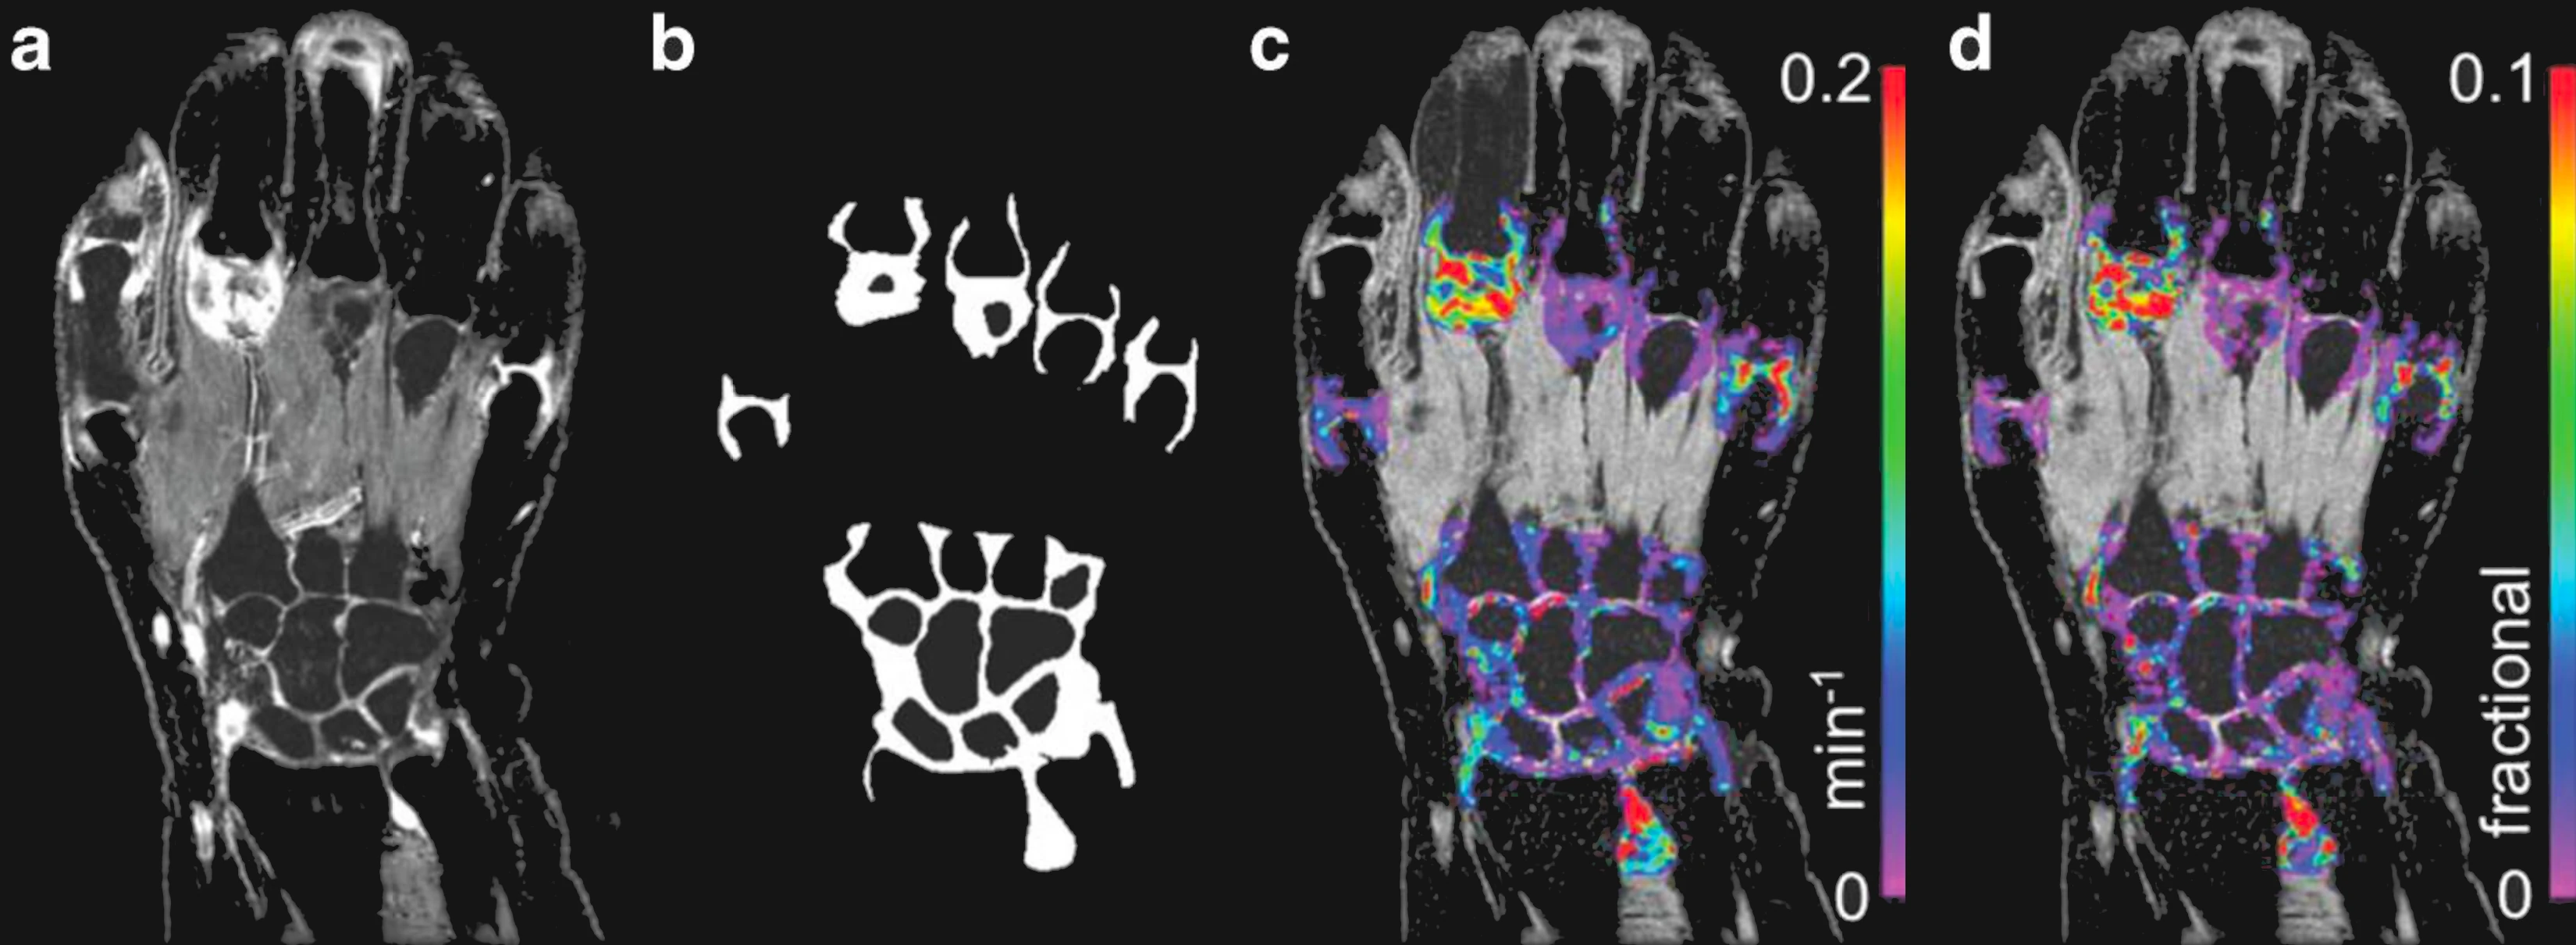

From study design to final reporting, Bioxydyn delivers repeatable MRI biomarkers that reveal tissue function, physiology and change. Our operational excellence and metrology help you compare results across sites, scanners and timepoints.

We're Bioxydyn - delivering quantitative MR biomarkers for pharmaceutical, biotech and academic studies. We combine scientifically leading methods with robust multi-centre study management and transparent analysis, turning complex images into repeatable measurements that support confident decisions.